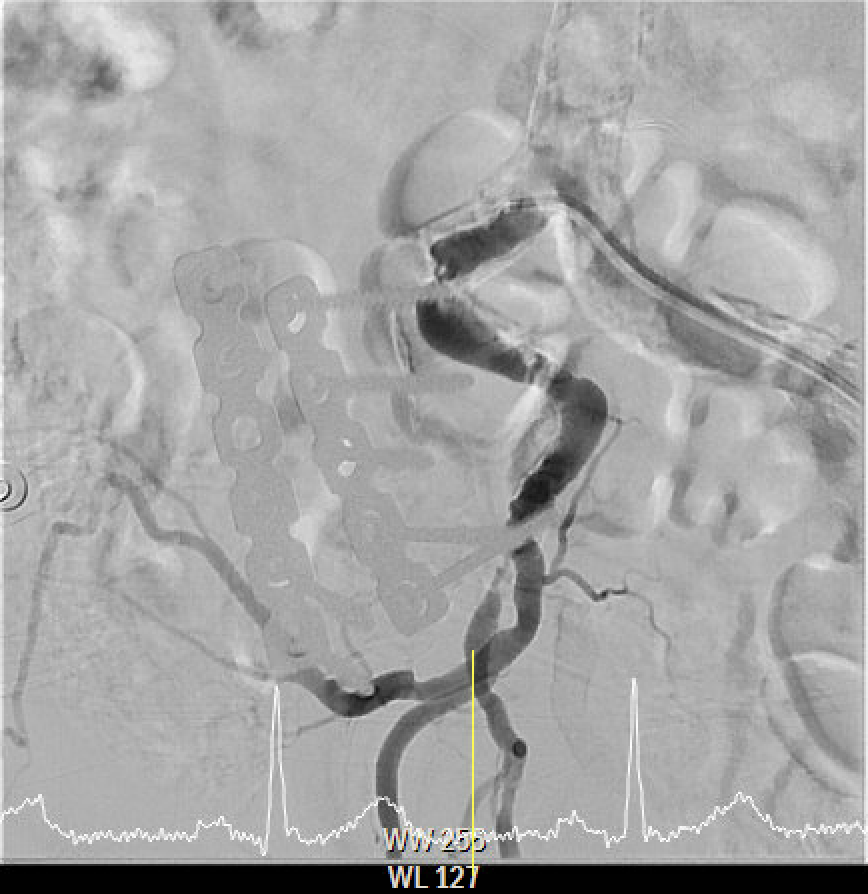

The angiography confirmed extensive Chronic Total Occlusion (CTO) of the right External Iliac Artery (EIA), Common Femoral Artery (CFA), and proximal Superficial Femoral Artery (SFA). The limb's circulation was critically dependent on collateral flow: the Deep Femoral Artery (DFA) was patent and supplying the distal SFA. Distally, a 50% stenosis was noted in the Popliteal Artery, but the Below-the-Knee (BTK) arteries were patent.

The procedure utilized a hybrid retrograde and antegrade approach. Retrograde access was established via a micropuncture kit under angiography guidance into the distal Superficial Femoral Artery (dSFA), but wiring attempts failed due to an intervening aneurysm, necessitating a switch to the antegrade route from the left brachial artery. A wire escalation technique, assisted by a microcatheter, successfully crossed the extensive CTO, and was met with retrograde microcatheter and externalized via the dSFA puncture site (retrograde access), establishing through-and-through wire access. Following initial balloon predilation and IVUS confirmation of diffuse thrombus, extensive angioplasty was performed. Definitive treatment involved deploying multiple overlapping GORE¢ç VIABAHN¢ç Endoprosthesis diameters (from 6mm to 8mm) from the dSFA proximally to the pEIA via left femoral access, effectively treating the long occlusion and excluding the aneurysm. A COOK Zilver Flex iliac stent reinforced the proximal landing zone. The stented segment was rigorously post-dilated up to 12 atm. The procedure concluded with a Drug-Eluting Balloon (DEB) PTA (BOSTON Ranger Paclitaxel-Coated PTA Balloon Catheter) to the dSFA to mitigate restenosis in the non-stented region. Final angiography confirmed good flow without distal embolization.